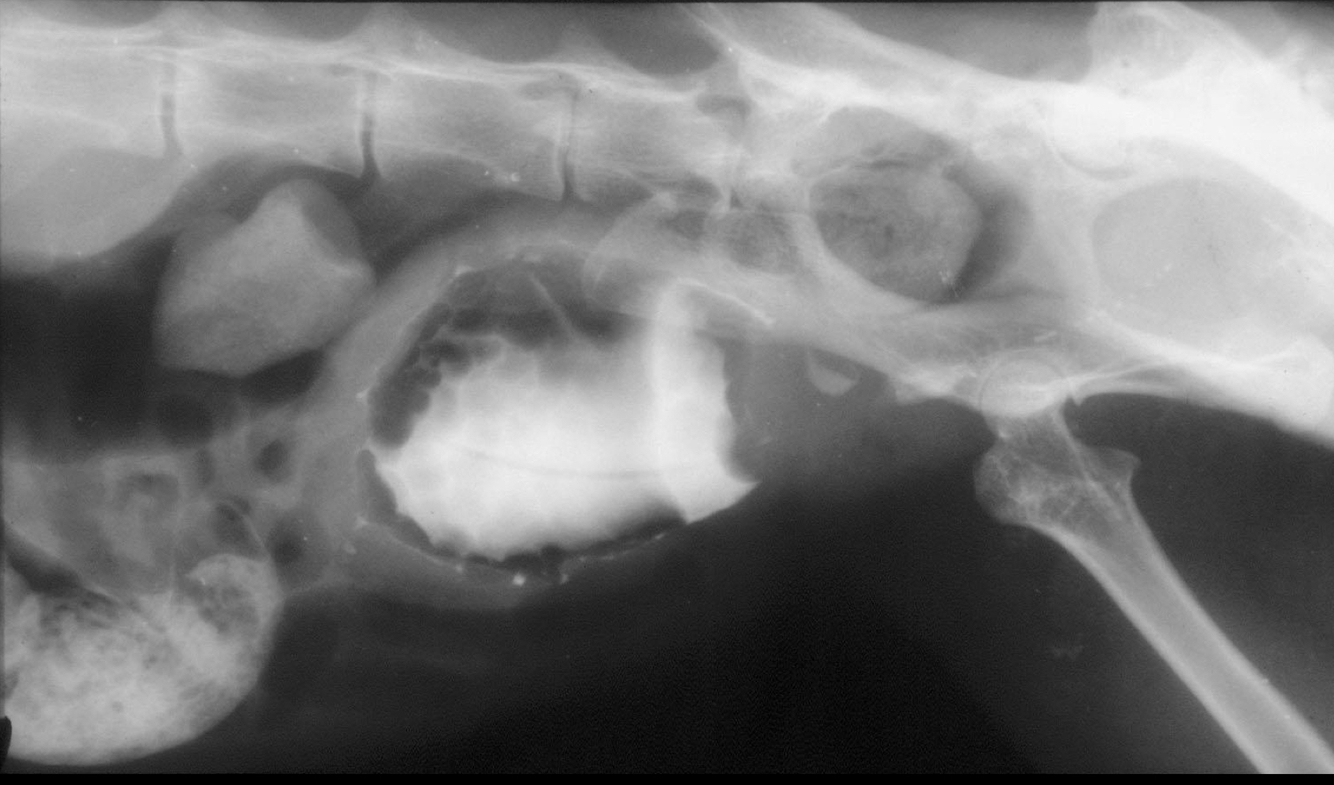

Q

What is likely causing the observed filling defect?

A

• filling defect at trigone, common spot for TCC

• wall thickening